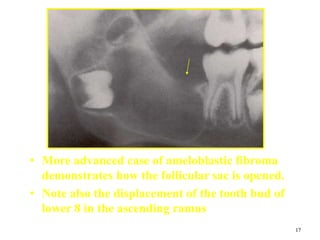

• More advanced case of ameloblastic fibroma

demonstrates how the follicular sac is opened.

• Note also the displacement of the tooth bud of

lower 8 in the ascending ramus